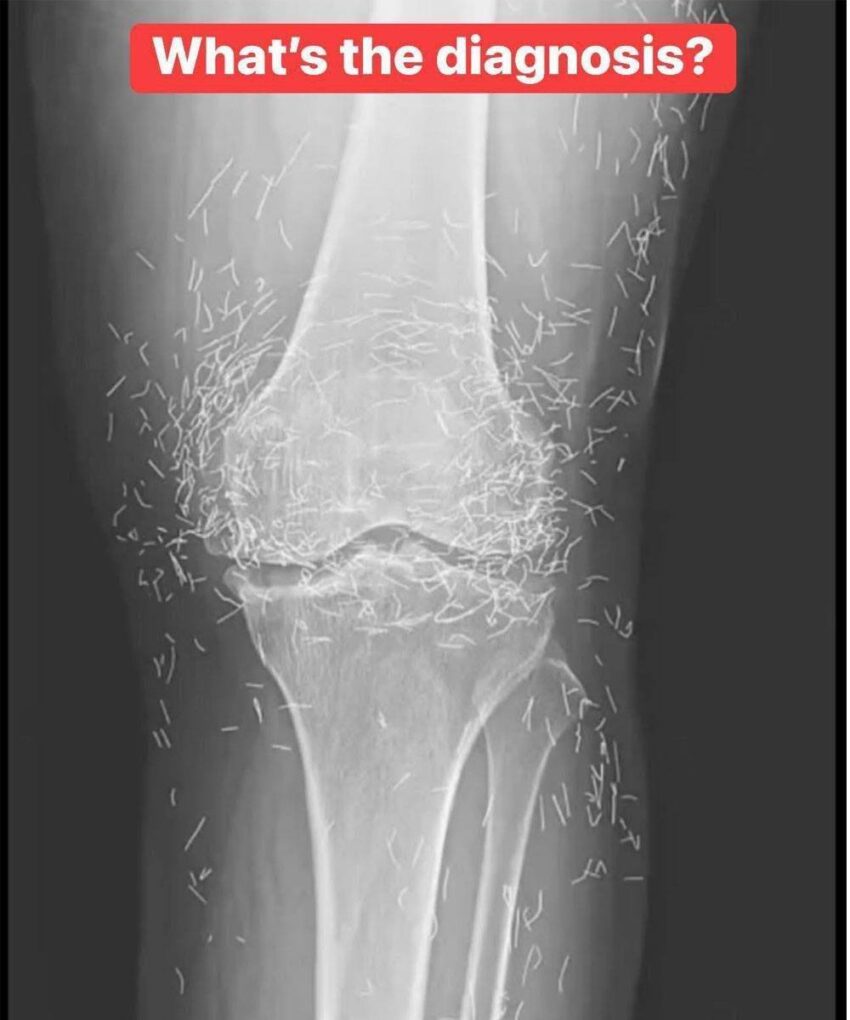

A 65-year-old woman came to the clinic after experiencing months of chronic knee pain.

Here’s a structured way to think about a 65-year-old woman with months of chronic knee pain:

1. Osteoarthritis (OA) – Most likely in this age group.

• Symptoms: pain worsens with activity, stiffness in the morning or after rest, swelling.

• Imaging: X-ray for osteoarthritis, MRI if soft tissue injury suspected